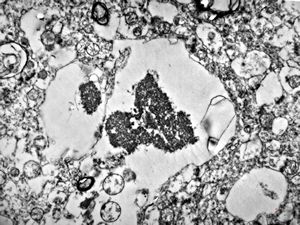

M,10y. | herpetic encephalitis